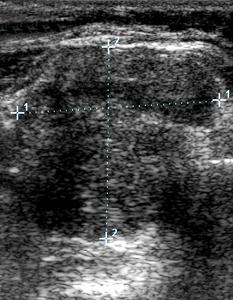

Допплерография щитовидной железы является важным методом для оценки ее функционального состояния, в частности, выделяет напряжение отдельных ее частей – долей, перешейка, крупных и средних сегментов, а также узлов. Это исследование проводится в двух режимах – ЦДК и ЭДК, а также двумя взаимодополняющими способами: 1) измерением внутреннего кровотока и 2) скоростью кровотока (пиковой систолической скорости в артериях щитовидной железы).

Анализ состояния лишь по серой шкале (В-режим) позволяет выявить структурные особенности (анатомическую и гистологическую организацию) щитовидной железы. Однако допплерографическое исследование значительно расширяет диагностику, позволяя оценить функциональное состояние измененных участков Всего органа.

• Специалист при УЗИ должен определять и фиксировать интенсивность кровотока, а также максимальную пиковую скорость в щитовидных артериях.